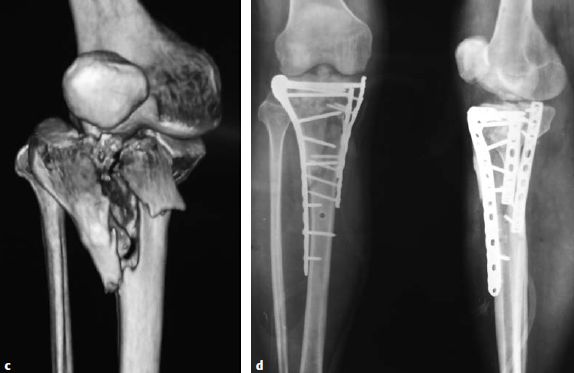

图片图6.8.1-23 a-e 后侧柱骨折

一名43岁男性骑摩托时受伤,他的左腿发生了胫骨平台的后侧柱骨折

a  术前X线;b  CT横断位显示内侧骨块累及了后侧柱,同时后侧中央存在关节面的塌陷;c  对这名患者使用倒L入路;d  一块4.5mm长钢板放置在柱上,T型钢板被用来支撑关节面的塌陷;e  术后X线